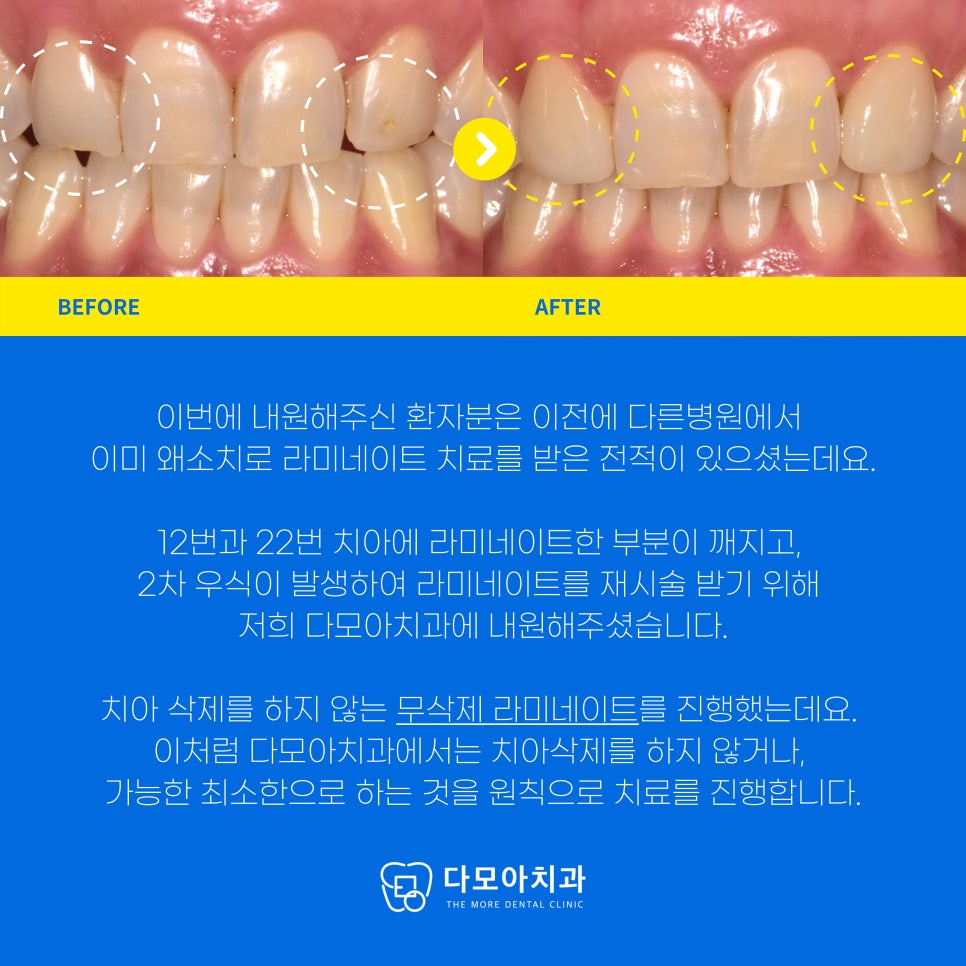

사진 속 라미네이트 한 부분이 깨지고,

2차 우식이 일어난 부분이 보이시나요?

최종적으로 라미네이트 치료를 완료한 사진입니다.

.

치아 삭제를 하지 않는

무삭제 라미네이트를 진행했는데요.

이처럼 다모아치과에서는 치아삭제를 하지 않거나,

가능한 적은 부분만 하는 것을

원칙으로 치료를 진행합니다.